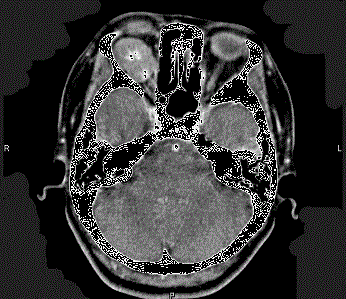

问题 41岁女性,右眼胀痛、眼球外突3月余,体检,发现低头时右侧眼球外突加重,CT检查如图所示,请选择最可能诊断 ( )

选项 A、右侧眶内神经鞘瘤 B、右侧眶内皮样囊肿 C、右侧眶内炎性假瘤 D、眼型格氏病 E、右侧眶内血管瘤

答案 E